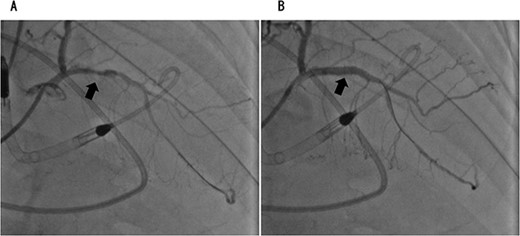

On the 2nd postoperative day, the patient experienced cardiac arrest because of a sudden drop in the saturation of percutaneous oxygen, after which his heartbeat resumed and he was intubated and placed on a ventilator. Transthoracic echocardiography showed left ventricular ejection fraction of 30%, diffuse hypokinesis of left ventricular wall motion and asynergy. Electrocardiography showed complete right bundle branch block, but no ST-segment elevation. Blood tests showed marked elevation of myocardial desensitization enzymes (CK: 362 U/L, cardiac troponin: 1143 pg/ml). Since ischemic heart disease could not be ruled out, angiography was performed. Coronary angiography revealed acute coronary syndrome with 90% occlusion of the left circumflex branch and 100% occlusion of the left anterior descending branch (Figs 3 and 4). The patient experienced shock and required VA-ECMO. However, the circulatory dynamics were unstable, and intra-aortic balloon pumping (IABP) was introduced. Furthermore, because the blood pressure could not be maintained with circulatory support from the IABP, we converted it to Impella 5.0. Assisted circulation with Impella 5.0 stabilized the patient’s blood pressure and allowed us to open the left circumflex and left anterior descending branches. VA-ECMO initially required an auxiliary flow of 1.2 L/min, which could be gradually reduced; Impella 5.0 initially required an auxiliary level of P7, which was reduced to P5 after VA-ECMO removal. VA-ECMO and Impella 5.0 were discontinued on the 6th and 8th postoperative days, respectively. He was eventually transferred by walking to a nearby facility for further rehabilitation 109 days later. One year later, the patient was recurrence-free of lung cancer.

Coronary angiography showed 90% occlusion of the left anterior descending branch (A). After the procedure, the occlusion was completely released (B).